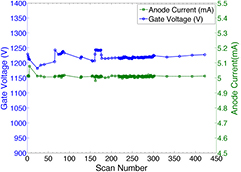

All 75 CNT sources in the array were characterized. Figure 4 shows the field emission properties of the CNT source measured at 80 kVp. As shown in figure 4(a), the emission current versus the applied cathode-gate voltage curve follows the Fowler-Nordheim equation for electron field emission (Gomer 1961). Once the cathode-gate voltage exceeds the CNT field emission threshold voltage, the emission current increases exponentially as the gate voltage increases. The measured transmission rates were consistent among all sources, with an average value of 70%. Figure 4(b) shows the anode current waveform for 5 different sources, measured using an oscilloscope, during source characterization. Each source outputs 5 mA of anode current during a 33 ms pulse width. As demonstrated in figure 4(b), the targeted specification of 5 mA anode current can be achieved with a programmable pulse width and good source-to-source consistency for all sources. The source stability database shows long-term stability for all the CNT x-ray sources used. The source stability for a typical cathode is plotted in figure 5. The cathode-gate voltage showed little change at 5 mA tube current for over 400 scans in four months. This stability is consistently observed from source to source, suggesting that the tube can be stably operated over a long time under this condition.

Standard image High-resolution imageFigure 5. Stability measurement of a CNT source over 400 scans during a 4 month period. The tube current (green dashed curve) was kept at 5 mA, the cathode-gate voltage (blue curve) barely changes in the test. The tube current fluctuation is less than 2% over the 400 scans, and no significant degradation of cathode-gate voltage was observed.

Download figure:

Standard image High-resolution imageThe source-to-source consistency for all 75 CNT x-ray sources was evaluated. The gate voltage needed to generate 5 mA tube current for each source was measured and is plotted in figure 6. All 75 sources output the desired current. The difference between the highest and lowest cathode-gate voltage for 5 mA tube current is approximately 400 V, which was readily compensated for by the control electronics. The source-to-source output consistency in one scan was also evaluated. Figure 7 shows the anode current from each source in a single tomosynthesis scan using 32 CNT x-ray sources. The results show that the CNT source array can output 5 mA anode current consistently from source to source, within 0.3% accuracy. For all the images acquired in this study, all sources were set to output 5 mA tube current. By changing the pulse width (in ms) of each source was on, the x-ray output (in mAs) for each projection image was easily controlled.